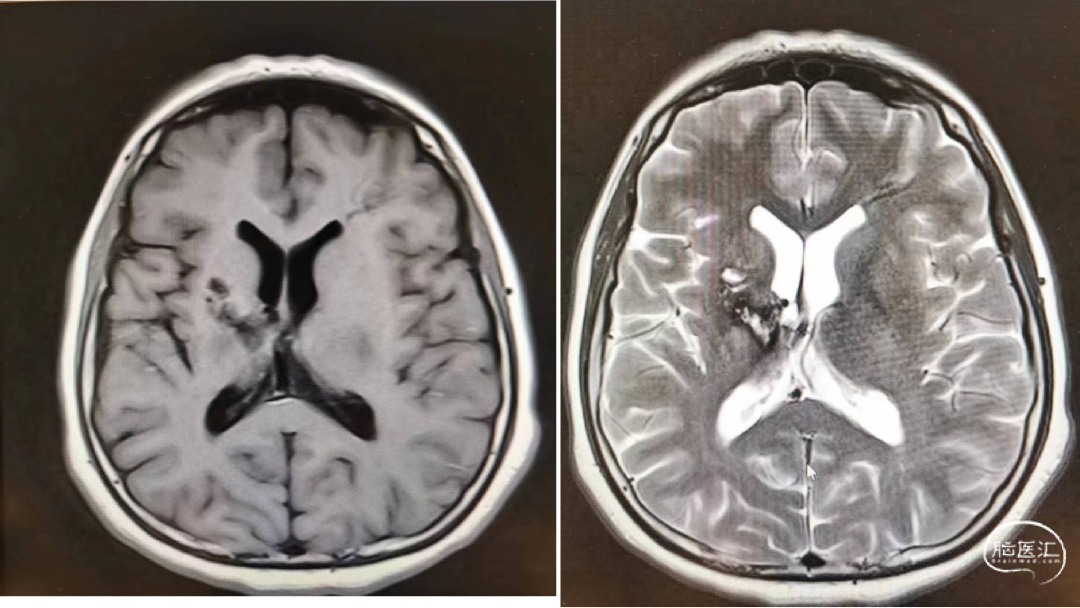

我院磁共振:右侧基底节动静脉畸形